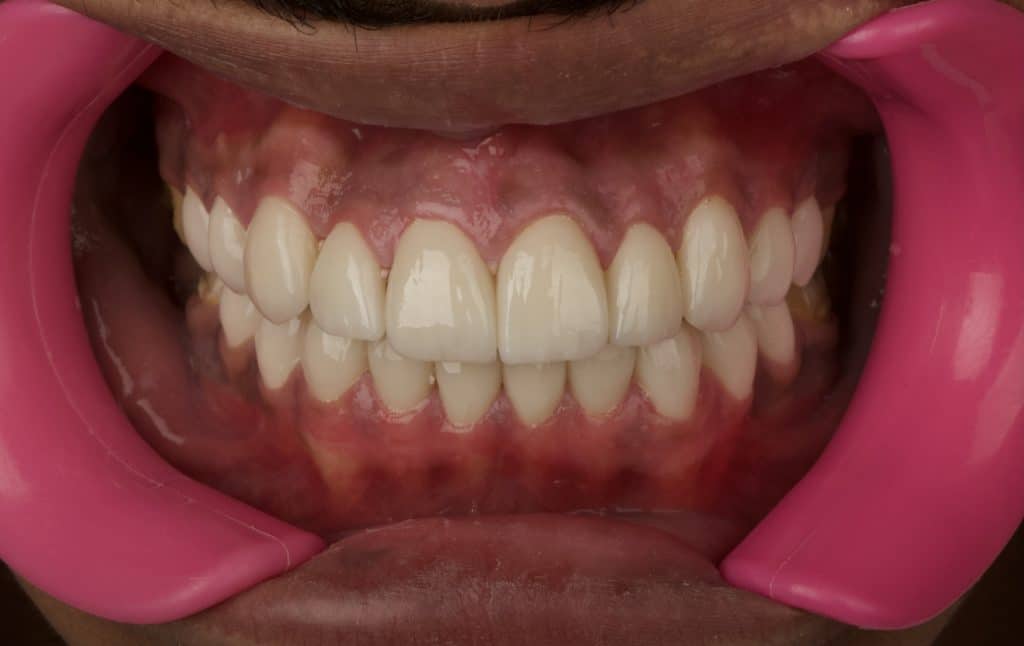

Final results 3 days after cementation

Before and after